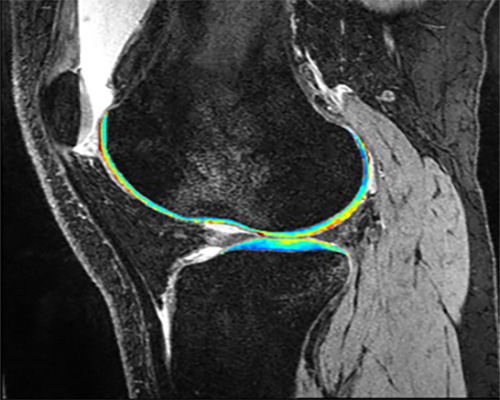

“Multi-Vendor Multi-Site Novel Accelerated MRI Relaxometry”

NIH (NIAMS)   —   R01AR075422

Li, Xiaojuan

“Imaging post-traumatic osteoarthritis 10-years after ACL reconstruction: a multicenter cohort study with quantitative MRI”

NIH (NIAMS)   —   R01AR077452

"Multi-Vendor Multi-Site Novel Accelerated MRI Relaxometry"

"Imaging post-traumatic osteoarthritis 10-years after ACL reconstruction: a multicenter cohort study with quantitative MRI"